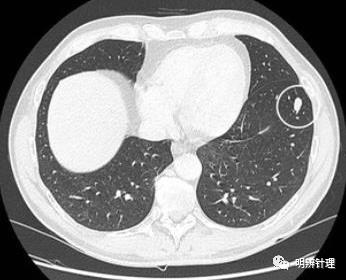

男性,54 岁,持续咳嗽。肺CT显示左肺下叶有一个清晰的椭圆形,泪滴样结节。结节缓慢增大。

诊断结果:典型类癌